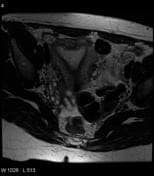

Septate uterus:

- Increased rate of pregnancy loss.

- Most common congenital abnormality of uterus

- Septate uterus: An angle of less than 75° between the uterine horns is suggestive of a septate uterus, and an angle of more than 105° is more consistent with bicornuate uteri.

- MRI:Imaging modality of choice for septate uterus